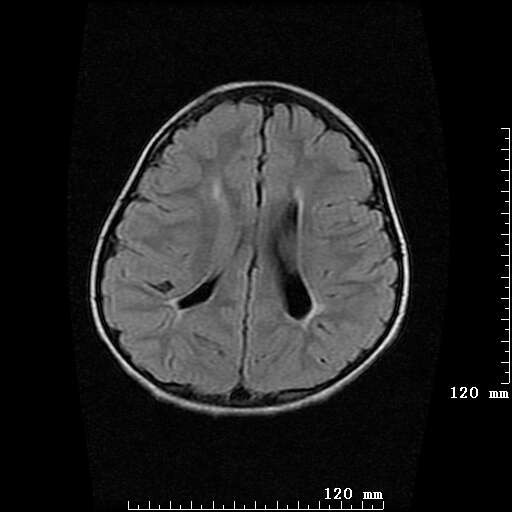

女,7岁,三岁才说话、走路。现智力尚可,走路不稳。临床怀疑大脑发育不全。

考虑 脑白质发育不良

脑折质变薄,双侧侧脑室稍扩张,支持考虑脑折质发育不良

侧脑室周围白质软化症。

考虑胼胝体发育不全,髓鞘形成不良。

支持考虑胼胝体发育不全,髓鞘形成不良。

侧脑室周围白质数量减少,侧脑室不对称性扩大,左侧侧脑室后角呈方形改变,脑沟加深,结合临床考虑脑室周围白质软化症(pvl)。期待结果!

只看出灰质异位

支持脑白质发育不良。